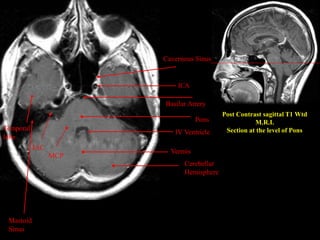

Post Contrast sagittal T1 Wtd

M.R.I.

Section at the level of Pons

Cerebellar

Hemisphere

Vermis

IV Ventricle

Pons

Basilar Artery

Cavernous Sinus

MCP

IAC

Mastoid

Sinus

ICA Temporal lobe Post Contrast sagittalT1 Wtd M.R.I. Section at the level of Pons Cerebellar Hemisphere Vermis IV Ventricle Pons Basilar Artery Cavernous Sinus MCP IAC Mastoid Sinus

• 39.